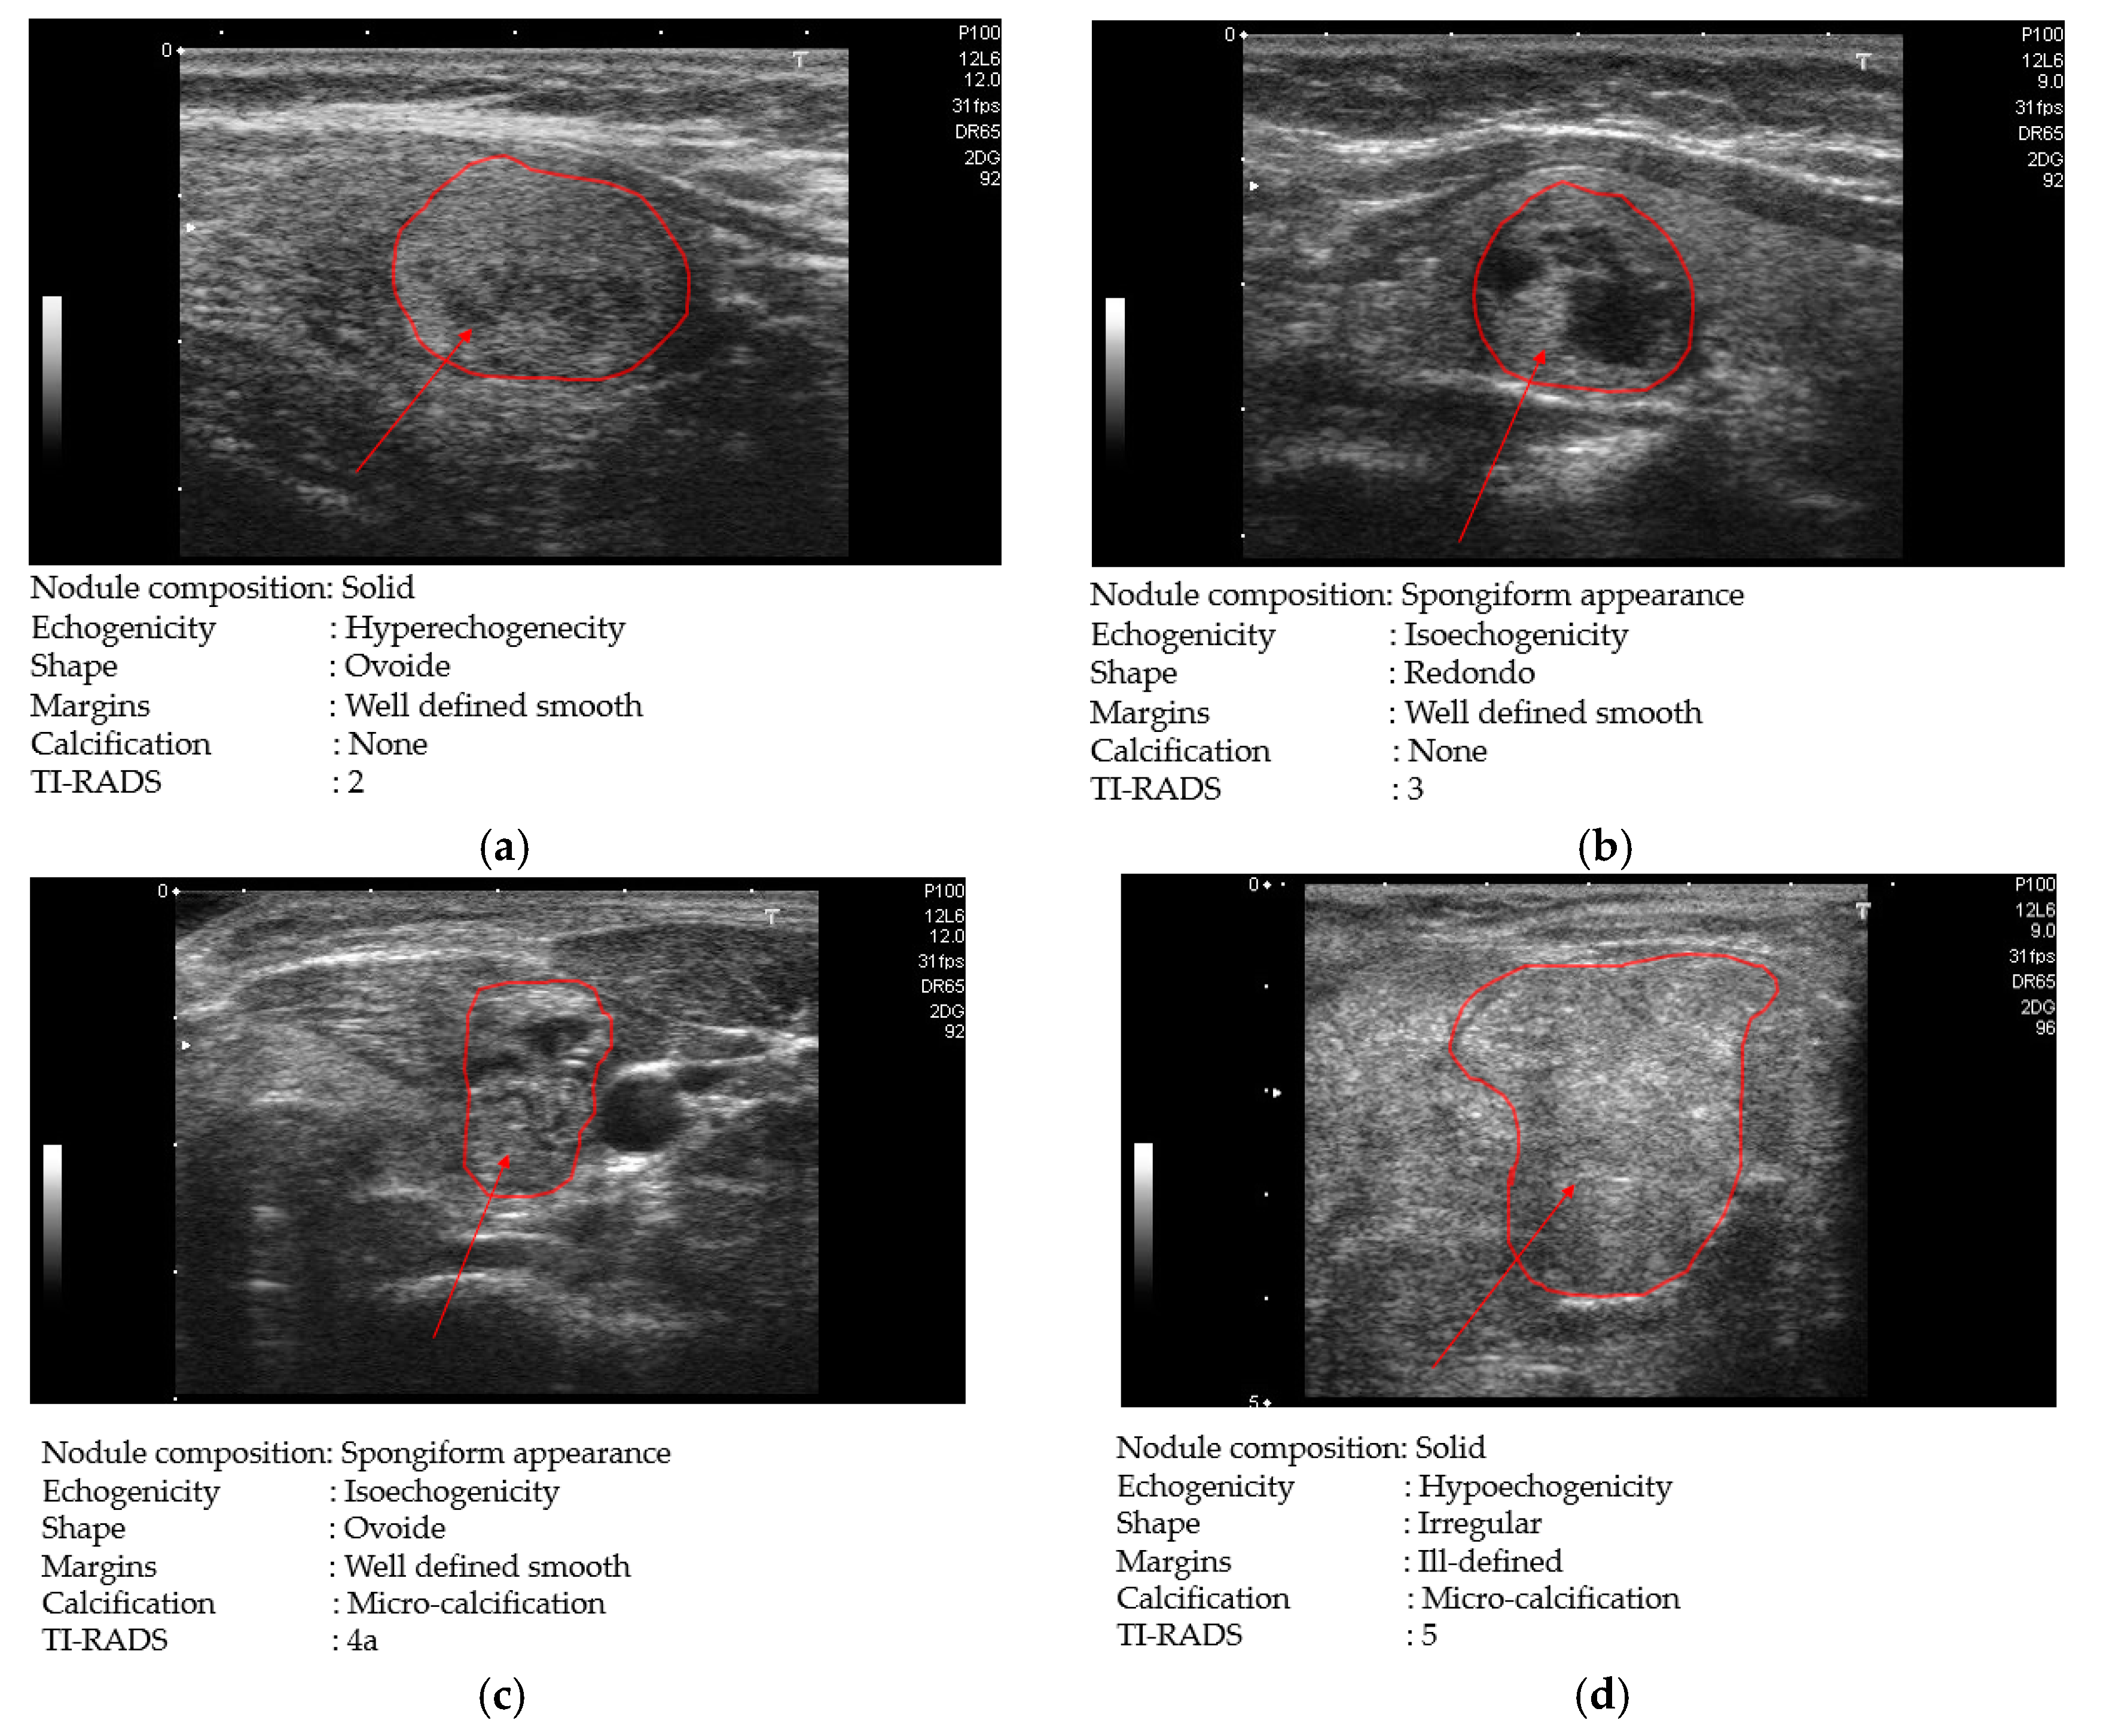

Based on its definition, the TI-RADS score takes one among six values {2, 3, 4a, 4b, 4c, 5} with scores of 2 and 3, indicating cases of benign and no suspicious ultrasound (US) features, respectively, while scores of 4a, 4b, 4c, and 5 indicate cases of one suspicious US features, two suspicious US features, three suspicious US features and five suspicious US features, respectively. Based on this definition, we consider the images with TI-RADS scores of 2 or 3 as the benign (negative) cases, while the images with TI-RADS scores of 4a, 4b, 4c, and 5 are the malign (positive) cases. However, the images with TI-RADS score of 2 and 3 do not provide other information of non-malignant thyroid pathologies, like Hashimoto and Graves’ disease patients. Consequently, the TDID dataset provides a total of 52 patients with benign cases and 246 patients with malign cases.

In Figure 10, we show some examples of ultrasound thyroid images in the TDID dataset. Figure 10a,b shows two benign case images with TI-RADS scores of 2 and 3, respectively; while Figure 10c,d shows two other malign case images with TI-RADS scores of 4 and 5, respectively. As shown in Figure 10c,d, the malign case images contain nodules with calcification phenomenon (round shape of texture with spotted white regions). Differing from these two case images, the benign case image in Figure 10a does not contain these features and it seems to be easily distinguished from the malign cases of Figure 10c,d. However, the benign case image with the TI-RADS score of 3 (Figure 10b) contains some similar texture features to the malign case image in Figure 10c,d such as round shapes of texture features, high illumination pixels, etc. As a result, this kind of benign case image is hard to distinguish from malign case images.

Figure 10. Examples of ultrasound thyroid images in TDID dataset: (a) a benign case image with thyroid imaging reporting and data system (TI-RADS) score of 2; (b) a benign case image with TI-RADS score of 3; (c) a malign case image with TI-RADS score of 4; and (d) a malign case image with TI-RADS score of 5.